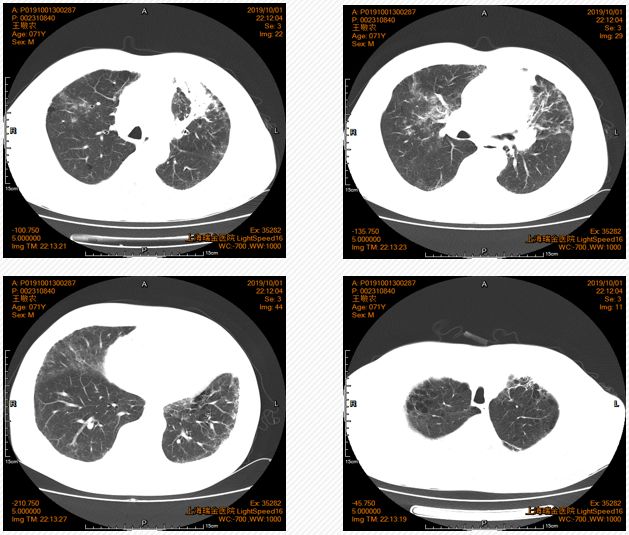

5. 胸部CT检查示:左肺门区可见团块状软组织密度影,截面大小约为3.7cm*2.4cm。

图1. 胸部CT检查